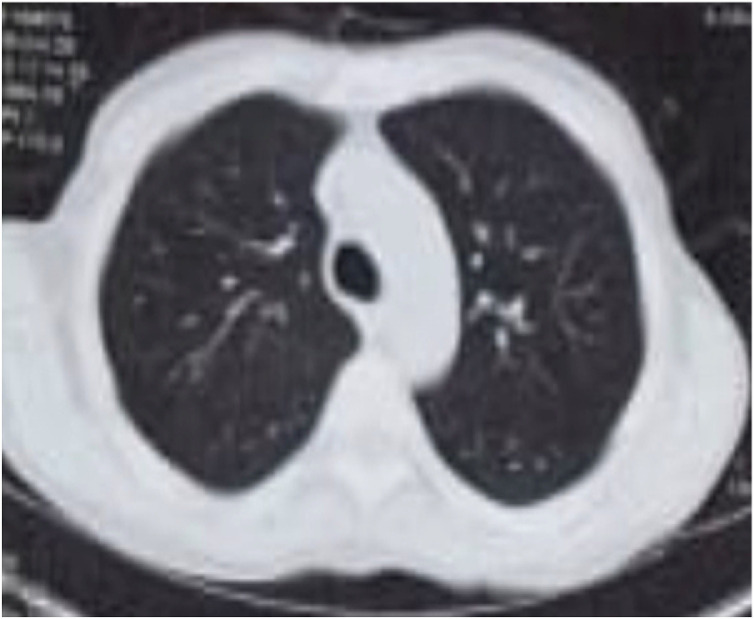

Fig. 1.

CT chest on May 2020 showing bilateral reticular pattern (first attack).